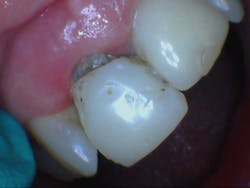

A quick radiographic assessment revealed missing coronal tooth structure/temporary material on No. 8 and rough edges for No. 9 (figure 1). Clinically, the temporary had broken resin on the buccal of the temp coping and was barely hanging on by a thread. Plaque and debris were heavy, accompanied by a fetid odor (figure 2).

Figure 1: Implants 8 and 9 with temps